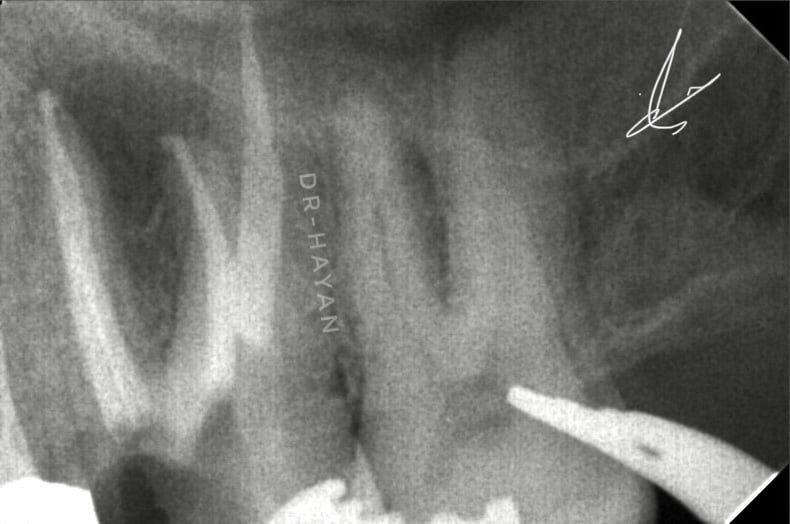

CBCT Showing large peri apical lesion related to bad endodontic treatment upper 6 and missing mb2

Peri apical x-ray